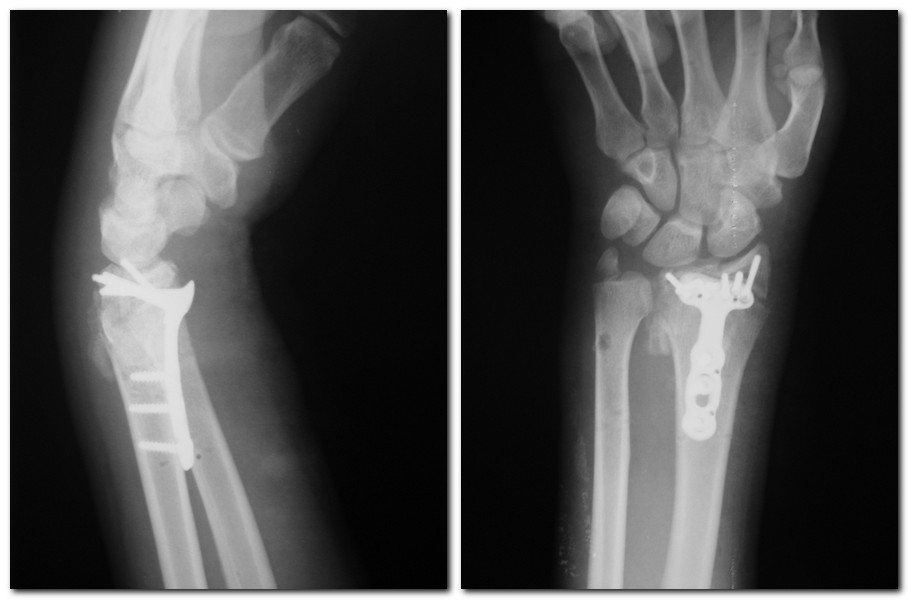

Доброго времени суток! Сегодня прооперировал пластиной DVR. Снимки прилагаю. Огромное всем спасибо за помощь!

С уважением, Васильев Н.Е.